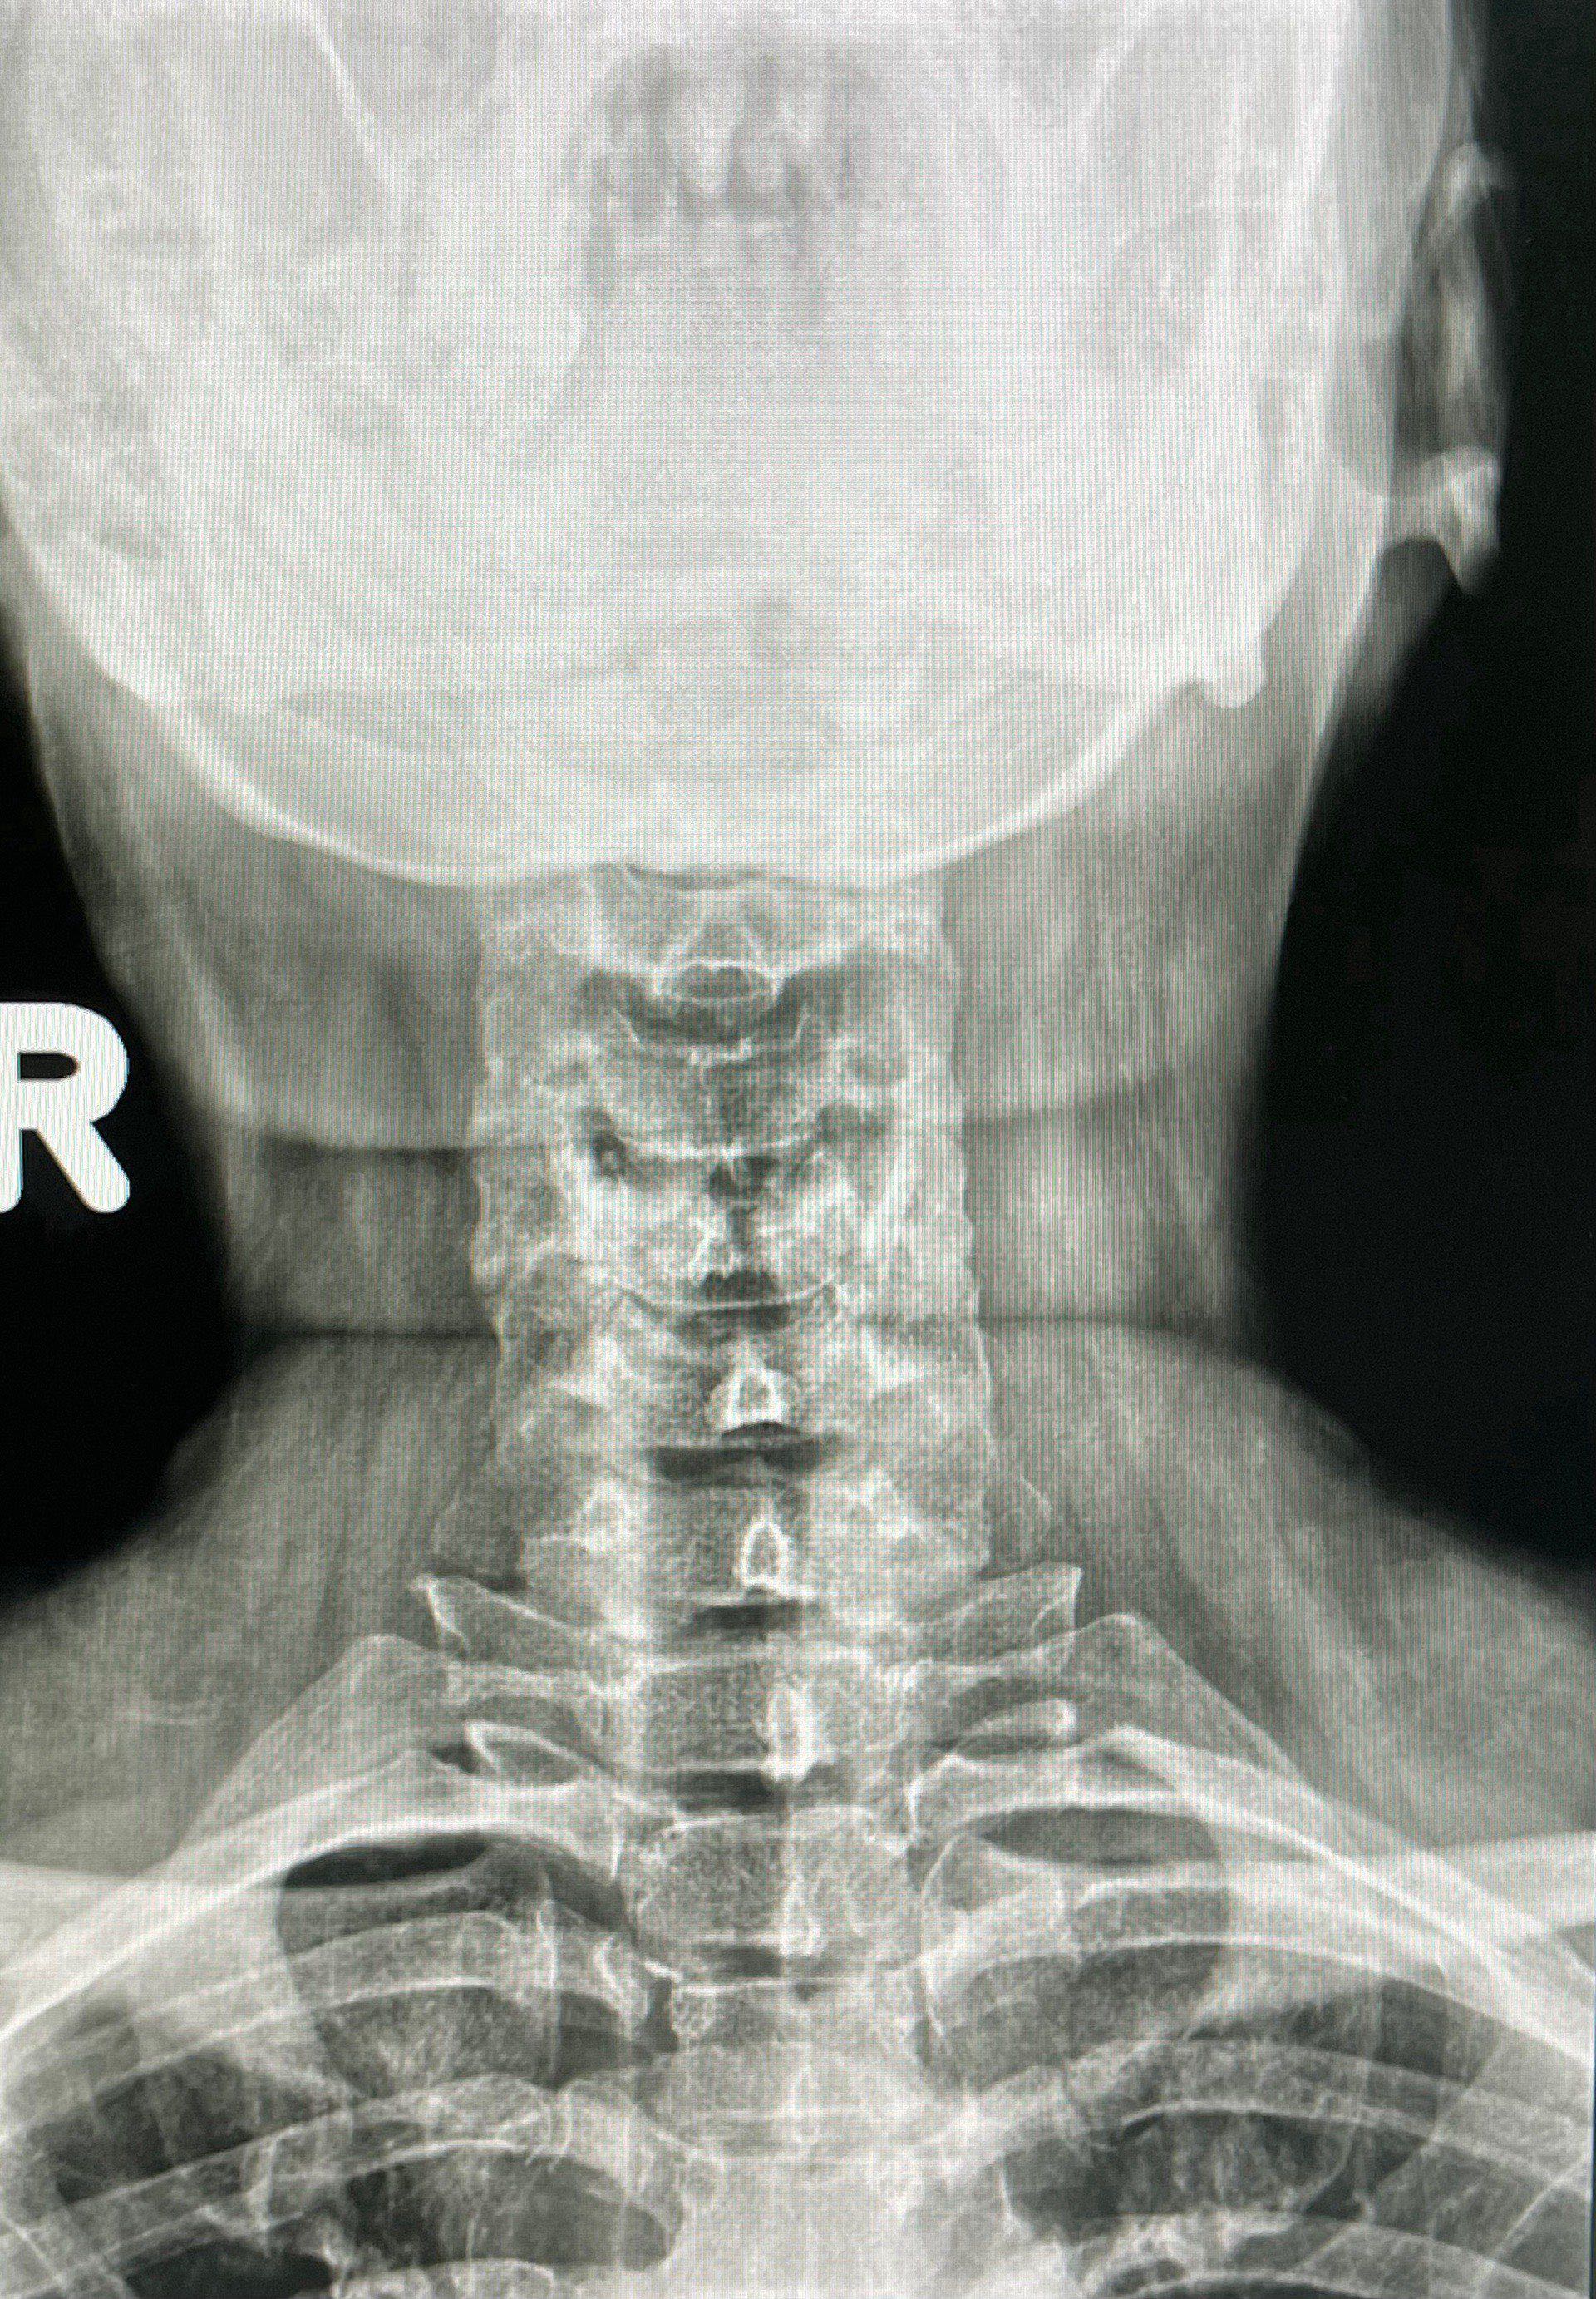

ปวดคอ ปวดหลัง หรืออาการปวดที่ร้าวไปถึงแขนหรือมือ นี่คือสัญญาณหนึ่งของ “หมอนรองกระดูกคอเสื่อม” อาการนี้ทำให้หลายคนสงสัยว่า “เราจะรักษาหายได้ไหม?” คำตอบคือ อาการเหล่านี้สามารถรักษาให้ดีขึ้นได้มาก และในหลายกรณีอาจสามารถกลับไปใช้ชีวิตได้อย่างปกติถ้าดูแลและรักษาอย่างถูกวิธีครับ

หมอนรองกระดูกคือชิ้นส่วนที่อยู่ระหว่างกระดูกสันหลัง ทำหน้าที่รองรับแรงกระแทกและช่วยให้กระดูกเคลื่อนไหวได้อย่างยืดหยุ่น แต่เมื่อเวลาผ่านไป หรือเมื่อมีการใช้งานมาก ๆ หมอนรองกระดูกอาจเสื่อมสภาพ ทำให้ไม่สามารถรองรับแรงได้ดีเหมือนเดิม และอาจมีการกดทับเส้นประสาทที่อยู่ใกล้เคียง จนทำให้เกิดอาการปวด ชา หรืออ่อนแรง

คำว่า “หาย” ในการรักษาหมอนรองกระดูกเสื่อมไม่จำเป็นต้องหมายความว่าหมอนรองกระดูกที่เสื่อมจะกลับมาเหมือนเดิม แต่การรักษาสามารถช่วยบรรเทาอาการ และช่วยให้คุณกลับมาใช้ชีวิตได้ใกล้เคียงปกติอีกครั้งได้ เราสามารถทำให้หมอนรองกระดูกที่เสื่อมอยู่ในสภาพที่เสถียรขึ้น ลดการกดทับเส้นประสาท และลดอาการปวดจนกลับมาใช้ชีวิตได้อย่างสบาย